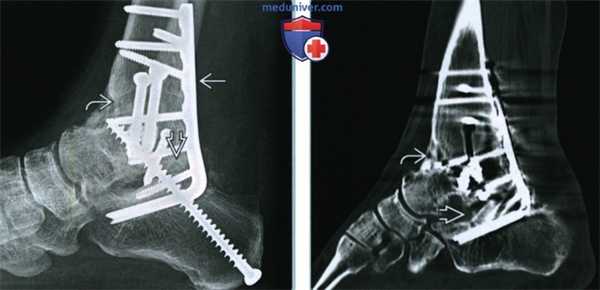

(Слева) При рентгенографии голеностопного сустава в передне-задней проекции на фоне таранной кости виден крупный отломок. Место перелома не визуализируется, однако единственным возможным источником фрагмента такого размера и формы может быть только медиальная часть тела таранной кости.

(Справа) У этого же пациента при рентгенографии голеностопного сустава в боковой проекции не соблюдена правильная укладка, однако перелом тела таранной кости все равно виден. (Слева) У этого же пациента при рентгенографии голеностопного сустава, выполненной в проекции суставной щели, определяется симптом двойного контура, обусловленный наложением тени отломка на тень тела таранной кости. Повреждения купола таранной кости не видны, поскольку линия перелома проходит позади верхней его границы.

(Справа) У этого же пациента при КТ в аксиальной плоскости позади таранной кости визуализируется крупный фрагмент, который был виден и при рентгенографии. Кроме того, спереди выявляется еще один фрагмент меньших размеров, но тоже достаточно крупный. Тяжесть переломов таранной кости при рентгенографии часто недооценивают, вследствие чего рекомендуется выполнять КТ. (Слева) При КТ в коронарной плоскости в костном режиме определяется оскольчатый перелом тела таранной кости, характеризующийся сагиттально ориентированной линией расщепления и выраженным вдавлением суставной поверхности. Такой перелом соответавует высокоэнергетической травме, при которой, как правило, выявляют еще и повреждения, обусловленные воздействием осевой нагрузки. В этом случае обнаружен перелом пяточной кости.

(Справа) При КТ в коронарной плоскости в коаном режиме визуализируются размозжение нижнего отдела тела таранной кости и разрушение заднего подтаранного сустава. Такая травма, не являющаяся типичной, возникла в результате падения с высоты.

2. Рентгенография при переломе тела и отростков таранной кости:

• Вертикальный перелом тела таранной кости по типу расщепления:

о Обычно со смещением; суставные поверхности неконгруэнтны

• Размозжение заднего подтаранного сустава (ЗПТС):

о Склерозирование, деформация суставных поверхностей ЗПТС

• Перелом латерального отростка:

о При рентгенографии выявляется с трудом

о Боковая проекция:

- Латеральный отросток таранной кости должен иметь форму буквы «V», соответствующей углу Гиссана

- При переломе латерального отростка отломок в виде буквы «V» может быть ротирован кпереди

- При оскольчатом переломе латеральный отросток может не визуализироваться:

Чтобы обнаружить латеральный отросток, следует тщательно соблюдать укладку

Задний край малоберцовой кости должен быть на уровне заднего края большеберцовой кости

о Передне-задняя проекция или проекция суставной щели:

- Латеральный отросток виден позади верхушки латеральной лодыжки

- В отростке может выявляться участок просветления

- Латеральнее отростка может выявляться костный фрагмент, отделившийся в результате отрывного перелома

- Отек мягких тканей наиболее выражен ниже верхушки латеральной лодыжки, что имитирует растяжение связок голеностопного сустава

• Перелом заднего отростка:

о Зубчатый край помогает отличить отломок от треугольной кости

о Как правило, смещение минимально

о Виден лишь в боковой проекции

3. КТ при переломе тела и отростков таранной кости:

• Перелом тела таранной кости:

о Как правило, сложный

о Часто повреждение ЗПТС обширнее, чем видно на рентгенограмме